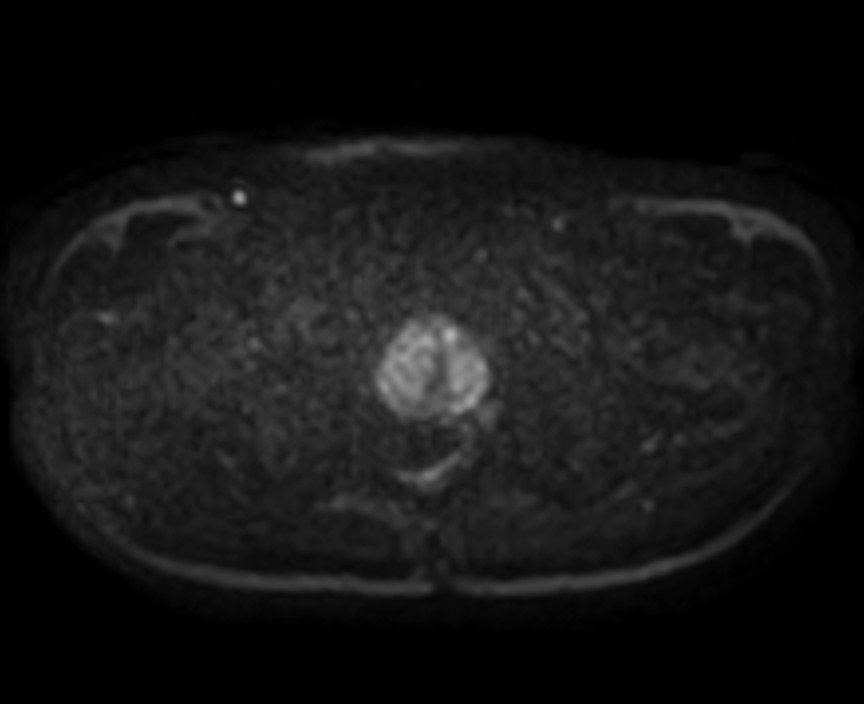

Fast Prostate imaging with SmartSpeed Precise

Kumamoto Chuo Hospital Japan

Used Solution